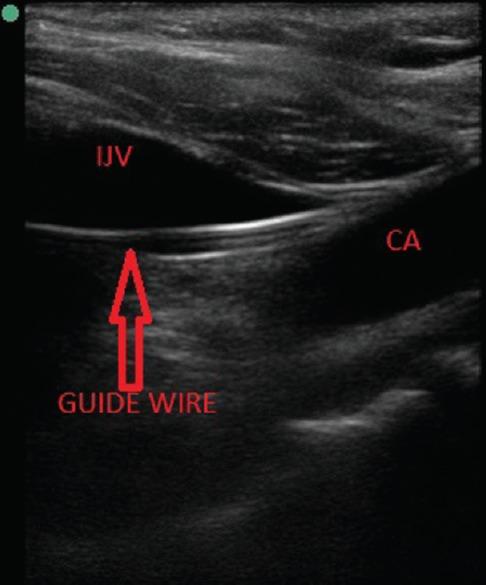

Ultrasound (USG) guidance has long been used for guiding central venous catheterization. USG provides direct visualization of needle puncture through the skin into the vein. Most of the time USG guidance is just limited to puncturing of the vein and seeing guidewire entering the vein while malpositioning of catheter occurs after that which is seen later on while checking chest radiograph. Repositioning of catheter after that becomes not only difficult requiring repeated chest radiograph to reconfirm position of catheter but also increases chances of infection with repeated manipulations. USG guidance can be used for tracing both guidewire and catheter during the procedure to prevent malpositioning of catheter, thus when done at the right time can prevent complication related to malpositioning and repeated manipulations. We used linear USG probe to check malposition of guidewire and microconvex probe to confirm position of central venous catheter.

超声(USG)引导长期以来一直用于指导中心静脉置管。超声可直接显示穿刺针经皮肤进入静脉的过程。大多数情况下,超声引导仅局限于静脉穿刺以及看到导丝进入静脉,而导管位置异常在此之后才会出现,后续在检查胸部X线片时才能发现。此后重新放置导管不仅困难,需要反复进行胸部X线片检查以重新确认导管位置,而且反复操作会增加感染几率。在操作过程中,超声引导可用于追踪导丝和导管,以防止导管位置异常,因此在合适的时间进行操作可预防与位置异常及反复操作相关的并发症。我们使用线性超声探头检查导丝位置异常,使用微凸探头确认中心静脉导管位置。